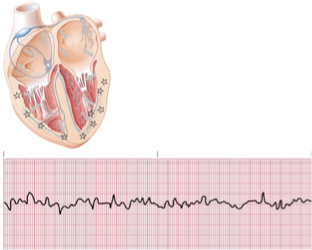

vfib

rate = no organized rhythm

rhythm = no organized rhythm

pacemaker site = numerous ventricular foci

p waves = usually absent

PRI = none

QRS = none

vfib etio and clinical significance

*Etiology

Wide variety of causes, often resulting from advanced coronary artery disease.

*Clinical Significance

Lethal dysrhythmia with no cardiac output and no organized electrical pattern.